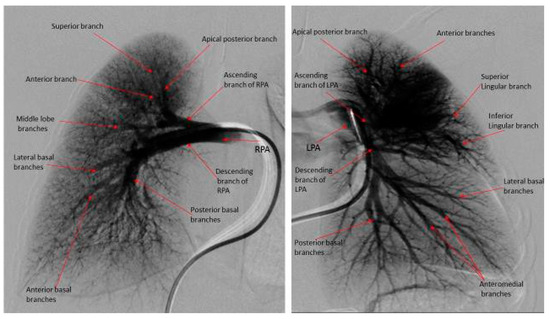

- Das, B.B.; Jadotte, M.M.; Mills, J.; Chan, K.C. Digital subtraction pulmonary angiography in children with pulmonary hypertension due to bronchopulmonary dysplasia. Med. Sci. 2019, 7, 26. [Google Scholar] [CrossRef] [PubMed]